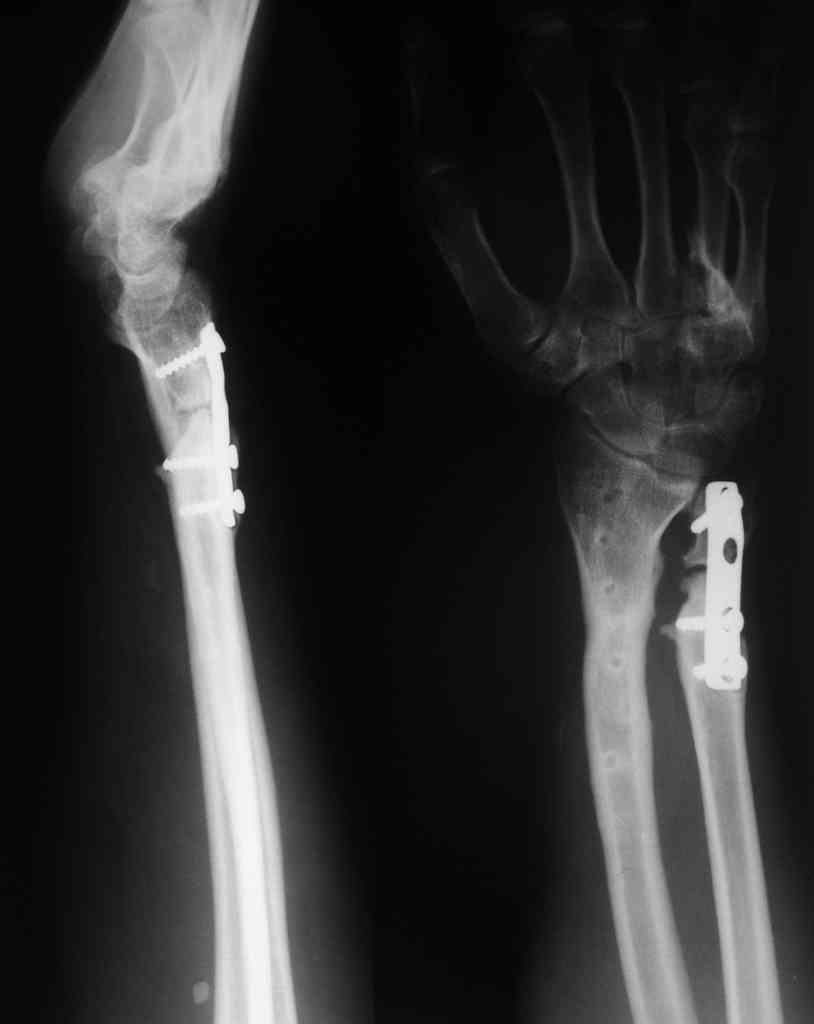

У больного/ой кроме перелома лучевой кости и шиловидного отростка локтевой, разрыв дистального радиоульнарного сочленения, перелом ладьевидной кости и ладьевидно-полулунная диссоциация.

Если позволите свое мнение, не стал бы лечить аппаратом эту травму, перелом луча не консолидировался: открытая репозиция+ костная пластика+ пластина, синтез ладьевидной кости, по возможности шов ладьевидно полулунной связки,

если восстановить связку не представляется возможным, фиксация 2 спицами.

Судя по показанным Рг граммам, очевиден посттравм. артроз лучезапястного сустава, проблема дистального радиоульнарного сочленения(TFCC).

Угол наклона лучевой фасетки в норме в пределах 10-15 градусов, на представленном боковом снимке -может быть чуть больше 15градусов. Выполнив

разгибательную остеотомию луча, ты поставишь фасетку в нейтральное положение и таким образом увеличится угол разгибания , но уменьшится сгибание. По сути, амплитуда движений останется такой же.